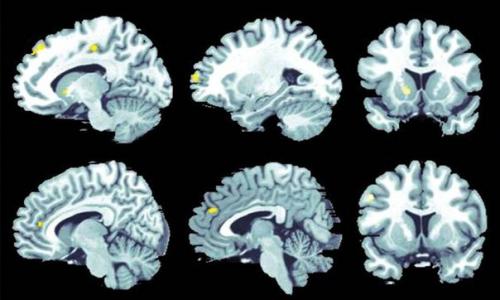

Работа программы основана на сочетании функциональной магнитно - резонансной терапии (фМРТ) с принципами машинного глубокого обучения. Система фиксирует локализацию и взаимосвязь электрических сигналов в головном мозге исходя из насыщаемости нейронов кислородом. При болезни альцгеймера избыток тау - белка провоцирует дефицит кислорода в нейронах.

В эксперименте ученые сравнили показатели 93 пациентов с умеренными когнитивными нарушениями и 101 пациента с сохранным интеллектом. В каждой области мозга было сделано 130 замеров с помощью фМРТ, после чего исследователи строили функциональные модели, демонстрирующие наиболее тесные связи. Посредством программы полученные результаты сопоставлялись с клиническими данными о поле, возрасте и генетических факторах риска испытуемых для составления прогноза о развитии болезни альцгеймера. Предсказательная сила методики превысила 80%.